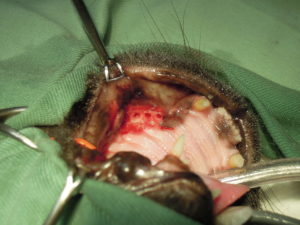

3.歯肉を切開して臼歯を分割して、

4.確実な抜歯を行い、